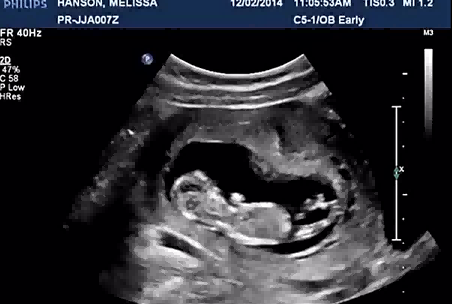

男宝b超影像上也有三条线这属于正常的生理现象。在怀孕期间做B超的时候会发现外生殖器有三条线,这属于正常的,这是由于性器官还没有完全的发育到正常状态所造成的,随着性器官不断的生长和发育,三条线也会逐渐的消失,因此男宝也有可能出现三条线的情况,孕妇在怀孕期间还需要多注意休息,同时还需要定期到医院做检查,及时了解宝宝的生长以及发育情况。

有些孕妈希望通过B超的手段来了解自己胎儿的性别,但有些影像上出现三条线的情况,并不一定代表是男孩,也有可能是女孩或其他因素导致的误差,因此不能作为判断性别的依据。以下是可能导致B超影像上出现三条线的原因:

1.与脐带有关:在B超影像上,出现的三条线与脐带位置有关。脐带是连接胎儿和胎盘的管道,通常呈螺旋状,因此在B超影像上形成类似三条线的图像,有时会被误认为是胎儿的性别特征。实际上这三条线并不代表特定的性别特征,只是脐带在B超影像上的表现。

2.与胎儿的体位有关:如果胎儿在子宫中的位置不正确,也可能出现三条线的情况。当胎儿的位置发生改变时,可能会导致B超影像上出现类似于三条线的图像。例如,当胎儿处于俯卧位时,B超影像上可能会呈现出类似于三条线的图像。

3.B超检查结果误差:B超检查结果受到多种因素的影响,包括羊水、设备和操作技术等。这些因素都可能影响结果的准确性。例如,B超仪器的分辨率、探测器质量、图像处理技术、图像传输技术等等,都会影响B超测羊水的准确度。

综上所述,男宝宝的B超影像也会出现三条线的情况,检查结果受到多种因素的影响,可能会存在误差和不准确性,因此,孕妇也需要了解B超检查的局限性,不要过分依赖检查结果,而是要听从医生的建议进行综合管理。。